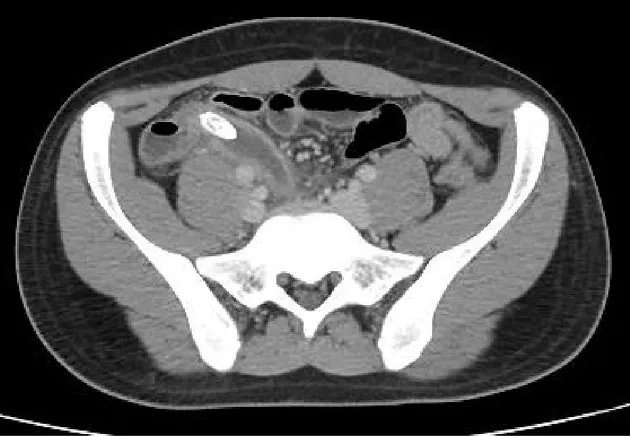

- First-line imaging: Ultrasound (children/women of childbearing age); CT if inconclusive

- Appendix diameter: >6mm on imaging suggests appendicitis

| Appendicitis | RIF pain, fever, raised WCC/CRP | CT: inflamed appendix >6mm |